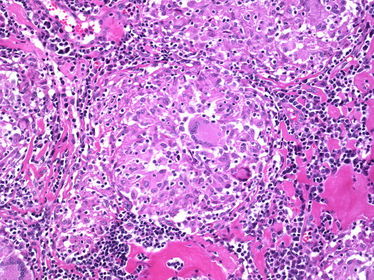

TISSUE TYPE: lymphocytes every where ... lumph node PATHOLOGY: granuloma with NO caseation .. langhan's cells (with horse shoe arrangement of nuclei) are seen and epithelioid cells.. DIAGNOSIS: Sarcoidosis N.B: NO caseation in contrary to TB. special charecters : Schaumann and asteroid bodies (Don't even think about seeing them xD).. may be isolated in a question .

Sarcoidosis